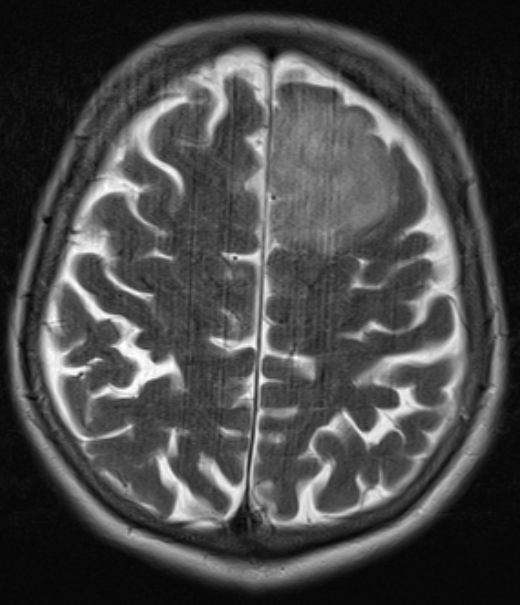

Rezidiv |

1 Monat nach Abschluss der Bestrahlung zeigt das MRT einen Tumorprogress an 2 Stellen. Die 2. Operation ergab ein Glioblastom mit geringer GMT-Methylierung.![]() |